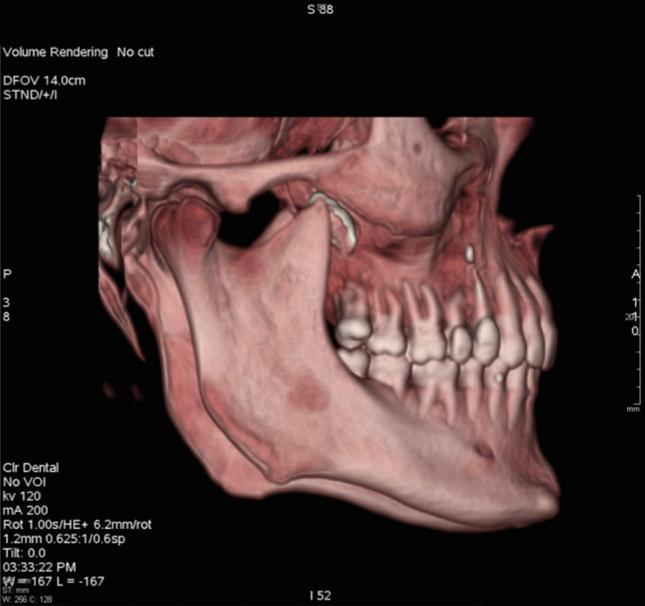

Foreign bodies found in the maxillary sinus include tooth roots, burs, dental impression material, root-filling materials, dental implants, and needles. The purpose of this paper was to present an unusual case of a large foreign body of endodontic origin (root-filling material) removed from the maxillary sinus. A 45-year-old generally healthy male patient reported to the Department of Conservative Dentistry with Endodontics of the Medical University of Silesia, because of orbital and buccal pain on the right side of his face and headaches in the preceding 6 months. Those symptoms were associated with the end of endodontic treatment of teeth 14 and 16. Periapical X-rays, including of teeth 14 and 16, showed the presence of root canal filling with extrusion of endodontic obturation material beyond the apices of tooth 14. In the case of tooth 16, a completely filled palatal canal and incompletely filled buccal canals were found. There was also an irregular dimness at the upper edge of the X-ray image. Panoramic radiography and computed tomography demonstrated a foreign body in the right sinus. Sinus exploration was performed via a surgical procedure conducted using topical anesthesia. The root apices of tooth 14 were resected, and foreign substance was removed. The practitioner did not correctly recognize a complication that occurred during endodontic treatment, which resulted in extrusion of endodontic material beyond the root apices of tooth 14. This case emphasizes the potential impact that an involved maxillary sinus may have on endodontic therapy. Detailed diagnostic identification based on the medical interview, physical and histopathological examinations, and diagnostic imaging allowed rapid surgical intervention and prevented local and general complications. It is important to realize that the range of the periapical X-ray projection is not always sufficient.

在上颌窦中发现的异物包括牙根、牙钻、牙科印模材料、根管充填材料、牙种植体和针头。本文的目的是介绍一例罕见的源自牙髓治疗的大型异物(根管充填材料)从上颌窦取出的病例。一名45岁的健康男性患者因右侧面部眼眶和颊部疼痛以及前6个月的头痛,前往西里西亚医科大学保守牙科与牙髓病科就诊。这些症状与14号和16号牙齿的牙髓治疗结束有关。包括14号和16号牙齿在内的根尖X线片显示根管充填,牙髓充填材料超出了14号牙齿根尖。对于16号牙齿,发现腭根管完全充填,颊根管充填不完全。X线图像上缘还存在不规则的模糊影。全景X线摄影和计算机断层扫描显示右侧上颌窦有异物。通过局部麻醉下的外科手术进行鼻窦探查。切除了14号牙齿的根尖,并取出了异物。该从业者未正确识别牙髓治疗期间发生的并发症,导致牙髓材料超出14号牙齿根尖。该病例强调了受累上颌窦可能对牙髓治疗产生的潜在影响。基于医学问诊、体格检查、组织病理学检查和诊断成像进行详细的诊断识别,有助于快速进行手术干预并预防局部和全身并发症。必须认识到根尖X线投影范围并不总是足够的。